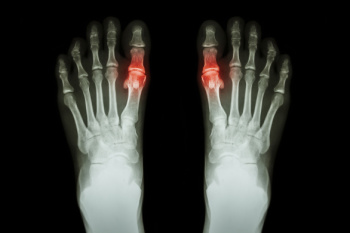

Gout can easily be identified by redness and inflammation of the big toe and the surrounding areas of the foot. Other symptoms include extreme fatigue, joint pain, and running high fevers. Sometimes corticosteroid drugs can be prescribed to treat gout, but the best way to combat this disease is to get more exercise and eat a better diet.